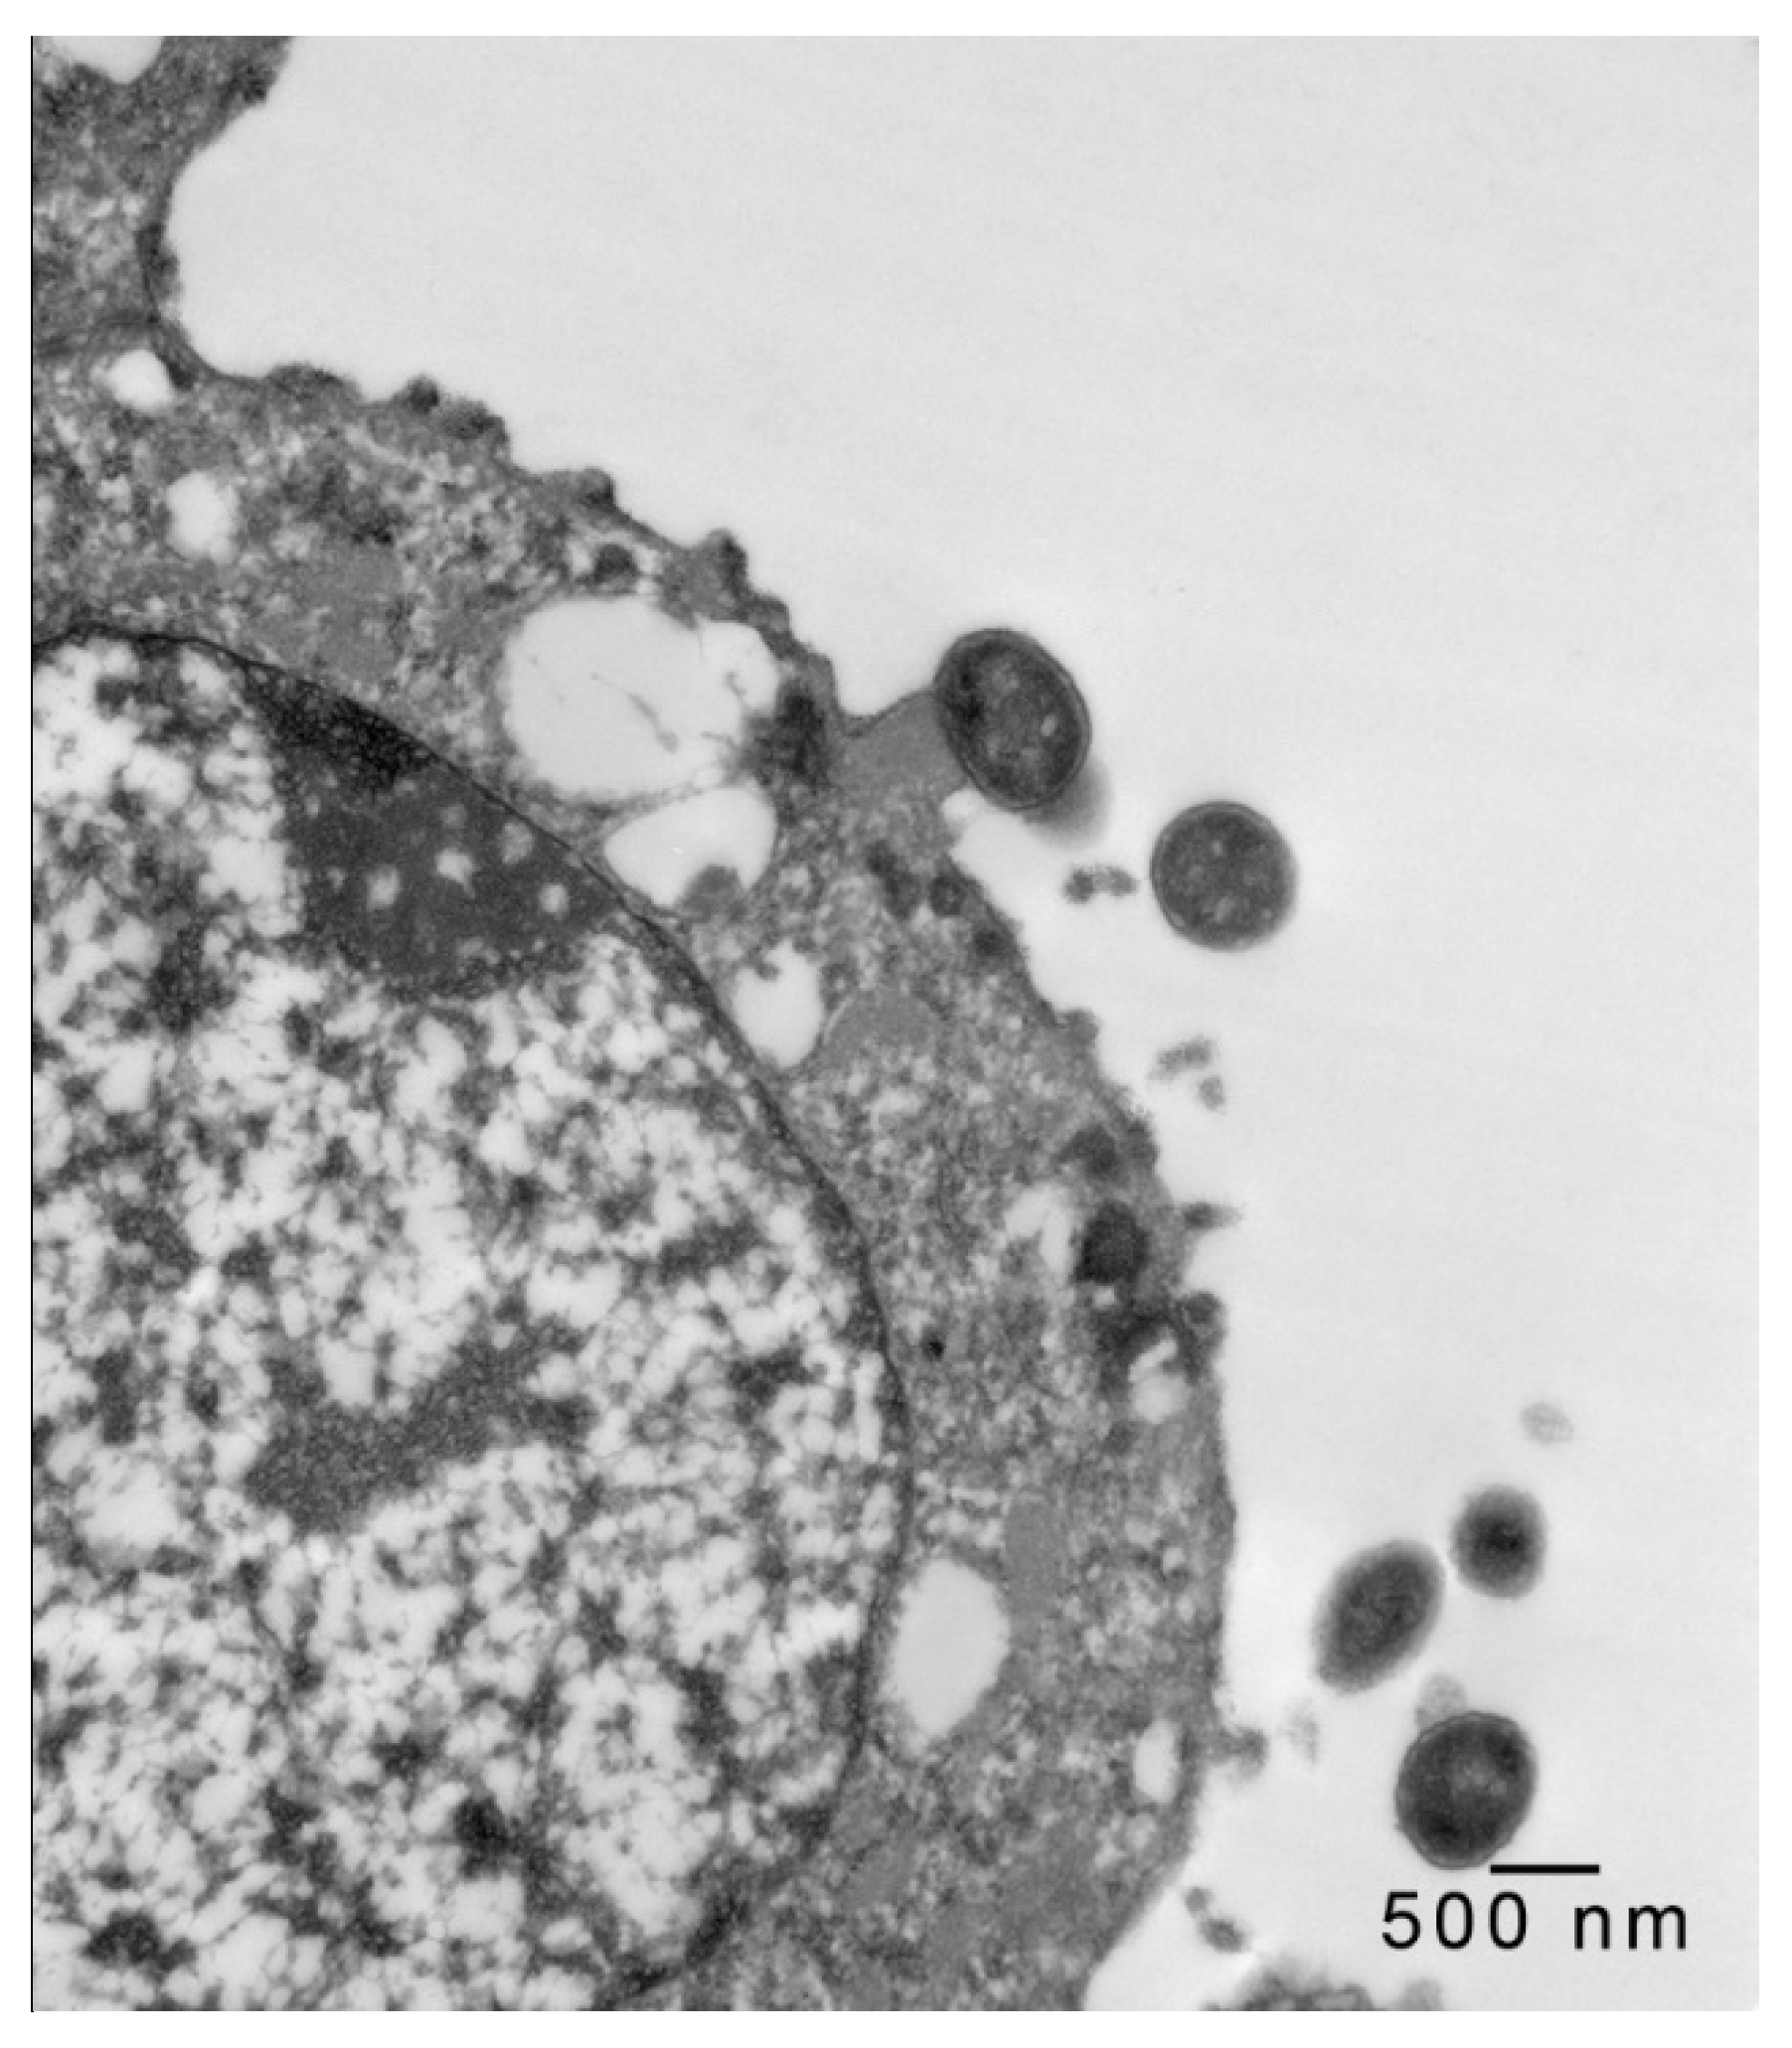

In 1-μm thick Araldite sections of urinary bladder prepared from tissues originally contained within the paraffin blocks [25], bacteria were detected only in piglet 15627 (Figure 1). In this piglet, in which bladder sections were oriented such that all three cell layers (basal, intermediate and superficial or umbrella) of the urothelium [26,27,28,29] were visible, bacteria, corresponding to bovine-origin strain 2891, were diffusely adherent to the apical surfaces of umbrella cells. By TEM, bacterial cells were found intimately attached to pedestals (Figure 2, Figure 3 and Figure 4). Some bacterial cells appeared to be attached to microplicae, preceding pedestal formation (Figure 4).

Figure 2.

Transmission electron photomicrograph of a thin section of a superficial epithelial (umbrella) cell of the urinary bladder of piglet 15627, 8 days PI with bovine-origin strain 2891. Five bacteria are seen in the section, with one attached to an actin pedestal near the center of the figure. Bar = 500 nm.

Morphologically, the pedestals to which bacteria in the urinary bladder of piglet 15627 were intimately attached were consistent with actin pedestals induced by EHEC and enteropathogenic E. coli (EPEC) in intestinal epithelium [24]. To our knowledge, this is the first report of intimate bacterial adherence and actin pedestals in the uroepithelium in any species. Staley et al. [30] first reported these lesions in 1969, describing them as attachment and microvillous exfoliation in ileal enterocytes of newborn, cesarean-derived piglets intragastrically inoculated with an E. coli strain belonging to a classical EPEC serotype, O55:H7. Takeuchi et al. [31] later described these lesions as occurring in rabbits inoculated with RDEC-1, a rabbit-origin O15:NM E. coli later classified as an EPEC [23]. Soon thereafter, the lesions were recognized in human infants with EPEC infection [32,33]. Moon et al. coined the term “attaching and effacing” to describe intimate attachment and effacement of microvilli in the intestinal epithelium of piglets and rabbits by EPEC [23]. Knutton et al. [34] first determined that the electron-dense material underlying the bacteria within the pedestals was filamentous actin. Over the past 50 years since the initial report by Staley et al. [30], numerous studies, many at the molecular level, have elucidated key bacterial and host factors involved in the pathogenesis of intimate attachment and pedestal formation [29].